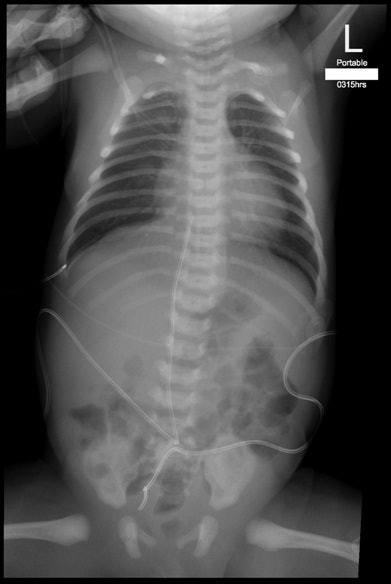

| Fingers of NICU staff are visible at upper left in this pediatric x-ray image. Image courtesy of Dr. Jordan Russell and study co-authors. |

The researchers evaluated 230 consecutive original anteroposterior portable NICU raw chest radiographs that had been acquired between December 2010 and March 2011. The raw radiographs, which included the cropped area of the image, were also compared with the cropped images in the PACS.

At RUH, a nurse immobilizes the neonate using one hand to stabilize the pelvis and the other hand to hold the patient's arms above the head during image acquisition. Most NICU incubators at the institution have cassette trays. In those that don't, the neonates are placed directly on a covered cassette.

Of the 230 radiographs audited in the study, 42% showed extraneous adult fingers in at least one of three study areas:

- Fingers in the direct beam that remained visible on PACS: 13%

- Fingers in the direct beam that were cropped out of the images before being sent to PACS for review: 10%

- Fingers in the coned area: 19%